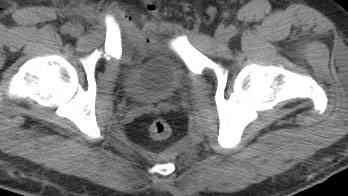

Уважаемые коллеги! опять вопрос по повреждению таза. Больной получил производственную травму 10 дней назад - удар балкой около 3 тонн в область верхней трети правого бедра и лона.

Был диагностирован перелом "типа бабочки" и повреждение уретры. Сделана цистостома. У нас в отделении 3 дня. Имеется огромная флюктуирующая гематома с "галифе"-образной деформацией обеих бедер. Пнкционно эвакуировали в несколько приемов из подфасциальных полостей на бедрах около 3 литров геморрагического отделяемого с последующей эластической компрессией. При пункциях выявлено сообщение полостей на бедрах - видимо через поравннуюдиафрагму дна и полость таза - при удалении крови справа уменьшался объем левого бедра. Какой то активности проявялять пока боимся - аппаратная фиксация через отслоенные ткани представляется чреватой нагноением, открытая фиксация в условиях такой гематомы тоже не радует. Хотелось бы услышать ваше мнение